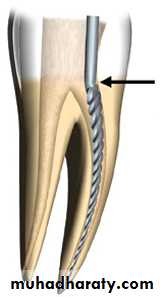

Root canal: is continuation of the pulp chamber inside the root start from canal orifice and terminate in the apical canal area.accessory canals: Lateral branching of the main canal located in the apical third of the root , at furcation of multirooted teeth.Lateral canal: Can be found any where along the length of a root at right angle to the main root canal.

Preparatory phase: in which an access opening is established, root canal content is removed and canal is prepared to receive the root canal filling material.

We have 2 types of endodontic cavity preparation 1) Endodontic coronal cavity preparation (access opening). 2) Radicular cavity preparation (root canal preparation).

Endodontic radicular cavity preparationOutline Form and Convenience Form (continued).

Toilet of the cavity: Meticulous cleaning of the walls of the cavity until they feel glassy-smooth, accompanied by continuous irrigation, & thorough debridement.Retention Form: It is recommended that the initial primary gutta-percha point fit tightly in the apical 2 to 3 mm of the canal. These nearly parallel walls (Retention Form) ensure the firm seating of this principal point.